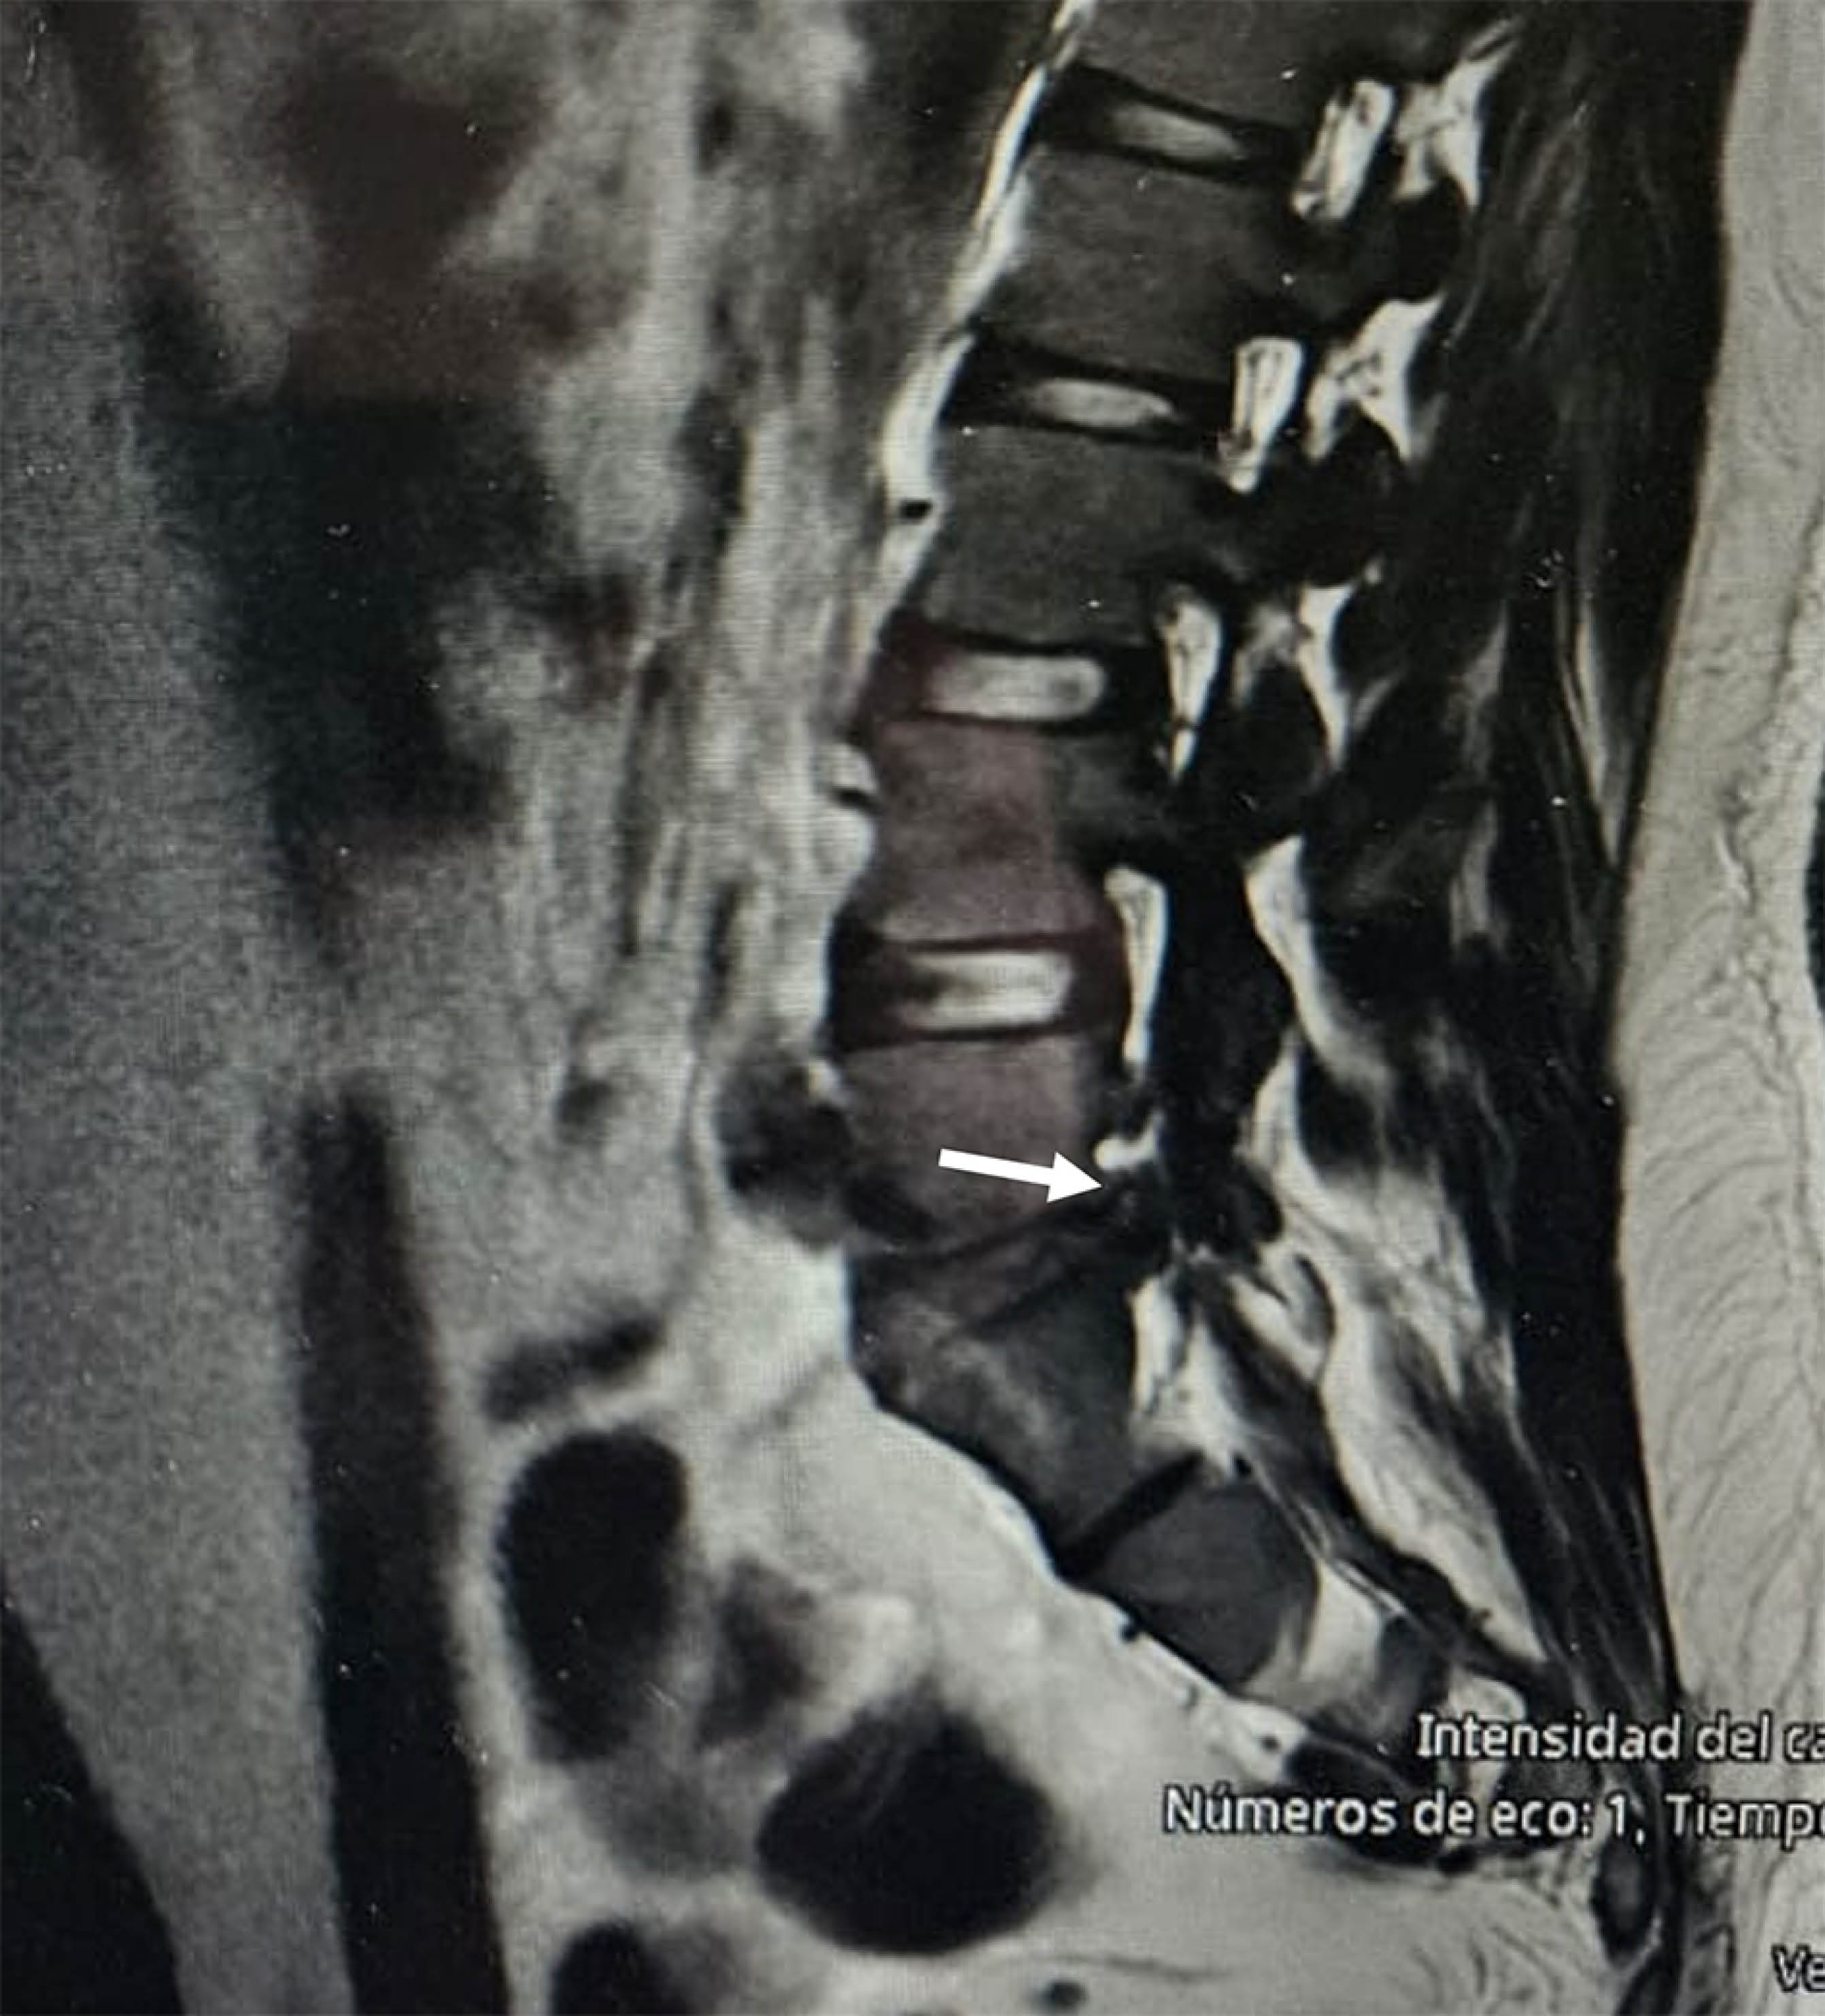

Hombre de 45 años, profesionista sedentario, quien 24 horas efectuó movimiento gimnástico de "rueda de carro", por lo que presentó sensación de "chasquido a nivel lumbosacro" seguido de lumbalgia con irradiación en territorio S1 izquierdo, en escala 9/10 en EVA, imposibilidad para marcha de puntas con pie izquierdo, paresia de glúteo medio y de tríceps sural izquierdo (2/5), la resonancia magnética mostró extrusión lateral masiva izquierda del disco L5/S1 con oclusión del foramen L5/S1 (Figuras 1 y 2). Se efectuó discoidectomía vía endoscópica; la evolución en cuanto al dolor fue satisfactoria, requirió ocho semanas de rehabilitación para lograr fuerza muscular 5/5 y marcha normal.

Figura 1